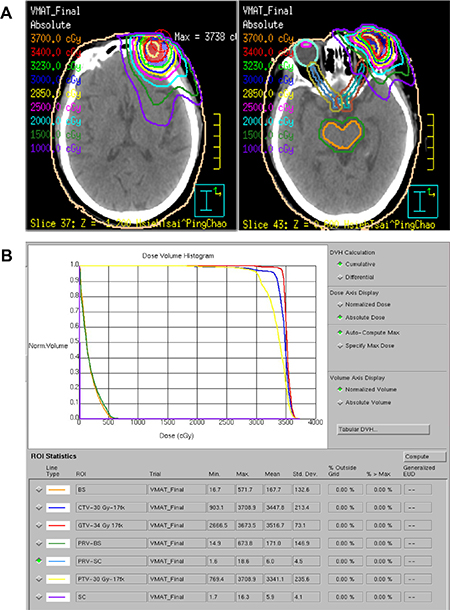

Among the patients with stage IE–IIE1 disease belonging to the radiotherapy-alone group, most patients were treated with a 6-MV photon beam for POALs of the orbit, extraocular muscle, eyelids, lacrimal gland, or conjunctiva. However, some received a 6–20-MeV electron beam for conjunctival lesions. Of the patients, 30 underwent 2-dimensional radiotherapy; 2 received a 3-dimensional conformal technique; 1 underwent intensity-modulated radiotherapy; and 1 underwent volumetric-modulated arc therapy (Figure 5) (Table 2). The radiation prescription dose ranged from 30 to 50 Gy (median dose: 40 Gy) in daily fractions of 1.8–2.0 Gy.

Figure 5: Isodose curves (A) and a dose-volume histogram (B) of the volumetric-modulated arc therapy plan using coplanar and noncoplanar beam arrangements displayed on the axial plane. The radiation prescription dose was 34 Gy (3400 cGy) in daily fractions of 2.0 Gy for one 79-year-old woman with left orbital MALT lymphoma. Abbreviations: GTV, gross target volume; CTV, clinical target volume; PTV, planning target volume. BS, brain stem; SC, spinal cord.